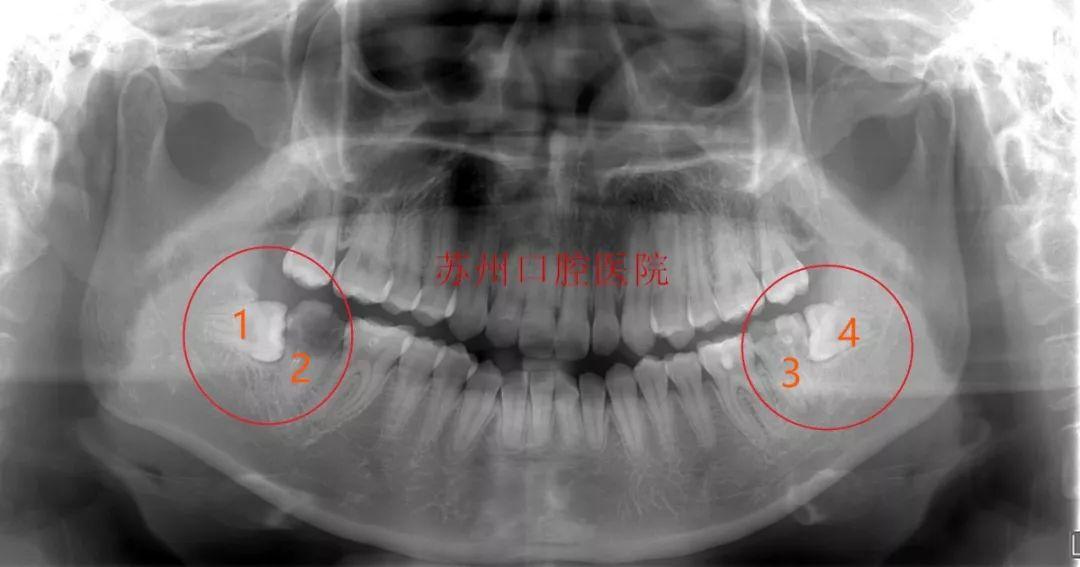

醫(yī)院牙體牙體牙髓科主任給患者做了檢查后,確定患者口內(nèi)情況:

常規(guī)方案是患者左右下頜都有兩顆橫位阻生的智齒,沒有及時(shí)拔除,現(xiàn)在這兩顆智齒引起前面7號(hào)牙的嚴(yán)重齲壞,按常規(guī)調(diào)節(jié)方案需要拔除兩顆智齒,以及智齒前方的兩顆7號(hào)牙,一共要拔除四顆牙齒,然后再種植兩顆牙。

自體牙移植方案:通過預(yù)判評(píng)估,進(jìn)行了自體牙移植,在拔除齲壞患牙后,用自身的智齒替代被拔除的患牙行使功能,大限度地保留了天然牙,又避免了種植牙。